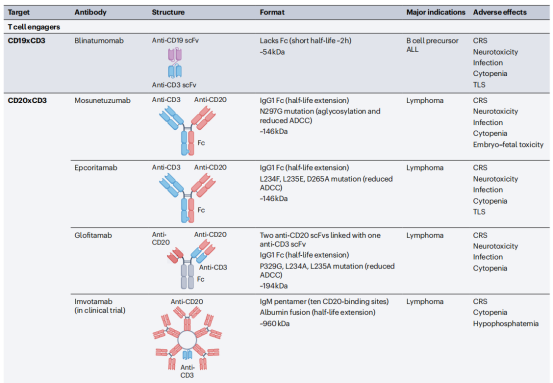

双特异性抗体可以结合两种不同的抗原或表位,抗原既可以定位在同一靶细胞上,也可定位在不同靶细胞上,针对两种不同细胞的双特异性抗体大多是T细胞连接物,将癌细胞与效应细胞交联,称为T细胞接合器(TCE)双特异性抗体。交联后,效应T细胞被激活,通过释放细胞毒性颗粒和淋巴因子来杀死结合的靶癌细胞。另一类双特异性抗体参与由同一靶细胞表达的不同抗原,例如两种不同的生长因子受体。这种双特异性抗体通过阻断通过目标生长因子受体的增殖信号,以及激活NK细胞和巨噬细胞来杀死癌细胞,从而杀死目标细胞。

常见的TCE双特异性抗体格式包括BiTE,Genmab,DART,Xmab,其中Blinatumomab使用BiTE格式。Glofitamab是一种用于淋巴瘤的的CD20xCD3双特异性抗体,并且具有独特的2:1的T细胞参与双特异性格式,它与传统的1:1靶细胞与CD3结合设计相比,这种格式具有更高的肿瘤杀伤作用。一般全长治疗性抗体使用的格式是IgG型,IgG有两个抗原结合位点,IgM是一个五聚体,它有10个抗原结合位点,与针对相同表位的IgG抗体相比,这提供了更高的结合亲和力。Imvotamab是一种CD20xCD3 IgM双特异性抗体,已在晚期B细胞恶性肿瘤患者中显示出完全缓解。

Blinatumomab由双特异性抗体所需的最小元素组成;一种靶向癌症的scFv(抗CD19)。Blinatumomab通过抗CD19scFv作用于B细胞,同时通过抗CD3scFv连接和激活T细胞,导致B细胞死亡。Blinatumomab在一系列B细胞恶性肿瘤中显示出活性,并被批准用于治疗B细胞前体急性淋巴细胞白血病(B-ALL)。